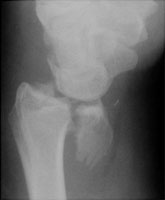

Reverse Barton Fracture

The reverse Barton fracture refers to an intraarticular fracture through the distal radius. Although it is similar in appearance to a Smith fracture, the Smith fracture is not intraarticular. The reverse Barton fracture involves the volar rim of the radius while the conventional Barton fracture involves the dorsal rim. The fracture is caused by direct trauma.

- Click on the image for a larger versionBOblique radiograph of the wrist. The intraarticular nature of this fracture can be appreciated.